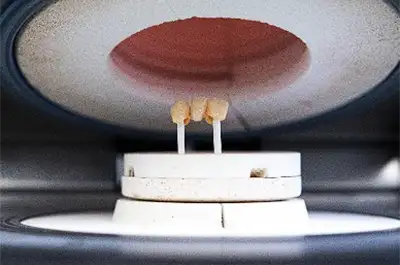

Ako je sve proslo u redu I pacjentu se sviđaju rezultati, doktor kreće sa pripremom pacjenta za rad. Brušenja se rade na temelju izdizajniranog wax upa. Nakon otiskivanja izbrušene situacije tehničar u laboratoriju kreće sa digitalnim dizajniranjem drugog prototipa od PMMA ili kompozita koji će poslužiti primarno kao privremeni zubi dok pacjent čeka svoj konačni rad, sekundarno kao test za otisak izbrušene situacije kako bi se mogli uvjeriti da je taj otisak dovoljno precizan za izradu konačnog rada. Ako smo uspješno prošli I tu fazu, tehničar nastavlja dizajnirati konstukciju na brušennim bataljcima I otisnutoj gingivi koji će nositi konačni rad te njezinom izradom ovisno o tome koji se material odabrao kao baza konstukcije. Ako se kao baza konstrukcije odabrao metal ili kompozit one se proizvode 3d printanjem. Ako se kao baza konstrukcije odabrao zircon, litij-disilikat ili PMMA tada se kontrukcije glodaju uz pomoć CNC mašina.

Nakon izrade konstrukcije te kada ju tehničar obradi I pripremi za slojevanje estetskog materijala, rad preuzima tehničar na odijelu estetike te uz pomoć dentalne keramike ili kompozita, materijala koji su se isprofilirali kao glavni estetski materijali, tehničar oblikuje estetski materijal u oblik zuba kakav je dogovoren s pacjentom na fazi wax up-a. Najteža stvar u ovom procesu koja je I jedna od najzahtjevnijih u laboratoriju je reproducirati boju tih zuba da taj protetski rad izgleda prirodno. Ključnu ulogu u dobivanju zadovoljavajuće boje ima niz faktora kao naprimjer odabir materijala za konstrukciju, boja bataljka ispod konstrukcije, veličina bataljka ispod konstrukcije, debljina konstrukcije, odabir estetskog materijala te boja preostalih zuba u pacjentovoj čeljusti koji nisu obuhvaćeni protetskom terapijom. Cilj je dobiti prirodnu graduiranost boje po slojevima iz dubinskih dentinskih slojeva do površinskih caklinskih slojeva, prirodnu fluorescenciju I transparenciju kakvu imaju prirodni zubi te zadovoljavajuću punoću boje I svijetlinu.